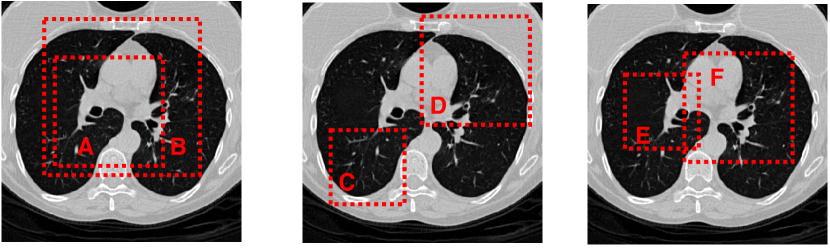

Data augmentation has been widely used in unsupervised representation learning and supervised learning [Parkhi et al., 2012, Donahue and Simonyan, 2019, Donahue et al., 2014]. A few existing approaches define the contrastive classification task as changing abd image’s structure. For instance, Hjelm et al. [Hjelm et al., 2018] and Bachman et al. [Bachman et al., 2019] used global-to-local view for contrastive learning as shown in the first example in Fig 2. Meanwhile, Oord et al. [Oord et al., 2018] and Henaff et al. [Hénaff et al., 2019] achieved neighbor prediction using the adjacency view (middle example, Fig 2). Those two methods can be view on the first two images on 2. Besides, we also introduce the over-lapping view which is the third image on Fig 2.

Figure 2: Three possibilities for random cropping. Dashed boxes are augmented views. Crops A, C, E views will have random color distortions applied while B, D, F will not change if the method (2) is chosen. All the cropped sections will be resized back to the original input image size. For the instance discrimination task, the goal, given B, D, F,is to, determine whether or not A, C, E are in the same instances.